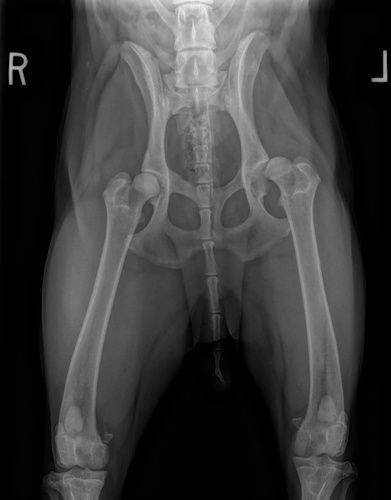

Hip Dysplasia

Hip Dysplasia in canines

Surgical Treatments of Hip Dysplasia

- Juvenile Pubic Symphysiodesis (JPS)

- Triple Pelvic Osteotomy (TPO)

- Total Hip Replacement (THR)

- Femoral Head and Neck Excision (FHNE)